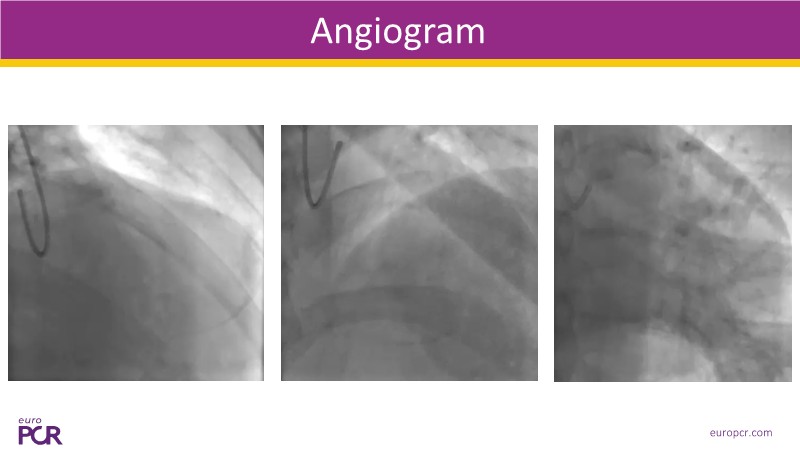

This EuroPCR 2025 session provides a comprehensive overview of drug-eluting balloons (DEBs) and their growing role in percutaneous coronary intervention (PCI). Gain a clear understanding of the clinical evidence and rationale supporting DEBs, including how these devices minimize metal implantation and effectively treat both standard and complex coronary lesions. The session highlights the mechanistic advantages of drug selection and sustained drug release technologies, with a focus on the SELUTION SLR DEB. Clinical updates include the LOVE-DEB study advocating a DEB-first approach in large vessel coronary artery disease, real-world performance data from the Malaysian registry, and practical case examples illustrating the transition to DEB-based PCI in clinical practice.